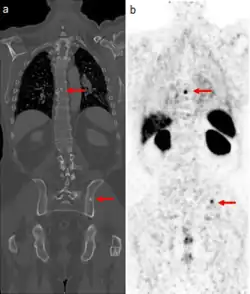

Medical images of a man's torso. Arrows indicate tumor metastases, visible as dots in the man's spine and pelvis, in both scans.

CT scan (left) and PSMA scan (right) showing prostate cancer metastases in the bone (red arrows). The dye used for PSMA scans is also absorbed by the kidneys, liver, and spleen (large dark objects at right).

The extent of cancer spread is assessed by MRI or PSMA scan – a positron emission tomography (PET) imaging technique where a radioactive label that binds the prostate protein prostate-specific membrane antigen is used to detect metastases distant from the prostate.[30][24] CT scans may also be used, but are less able to detect spread outside the prostate than MRI. Bone scintigraphy is used to test for spread of cancer to bones.[30]